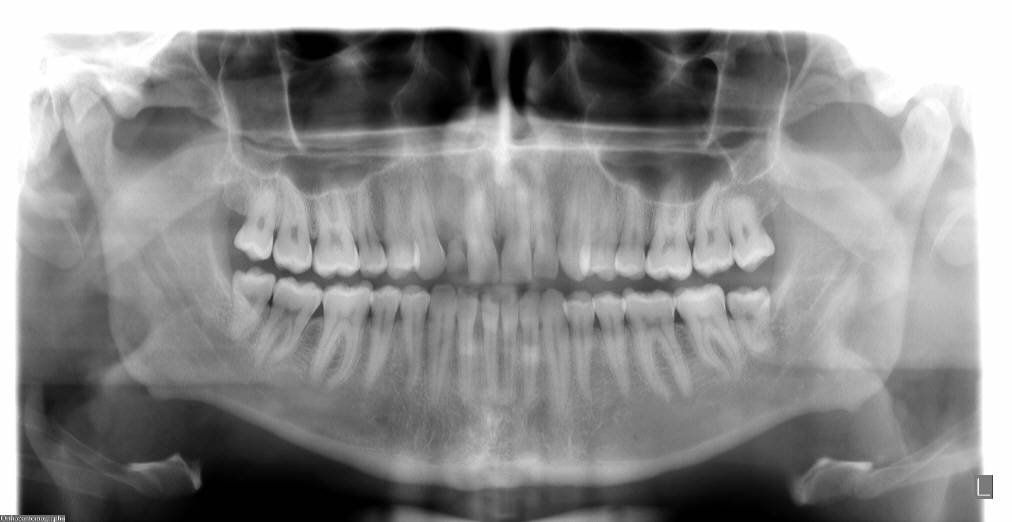

L'ortopantomografia è una tecnica diagnostica usata per l’analisi di entrambe le arcate dentali con una singola scansione a raggi X.

Fornisce informazioni molto utili per:

- Valutazione dello stato del cavo orale prima di un trattamento odontoiatrico.

- Diagnosi e pianificazione del trattamento di malattie dentali.

- Valutazione dello stato della dentizione nei soggetti in età di sviluppo.

- Valutazione ortodontica pre e post operatoria.

- Valutazione di carie interdentali, carie recidive, granulomi .

- Evidenziazione di eventuali malformazioni dentarie o denti inclusi.

- Ricerca di lesioni ossee, infiammatorie, cistiche a carico degli alveoli e delle strutture ossee circostanti.

- Ricerca della causa di una odontalgia misconosciuta.

- Valutazione della articolazione temporo-mandibolare in caso di anchilosi o disfunzione.

- Diagnosi di neoplasie delle ossa mascellari e mandibolari.